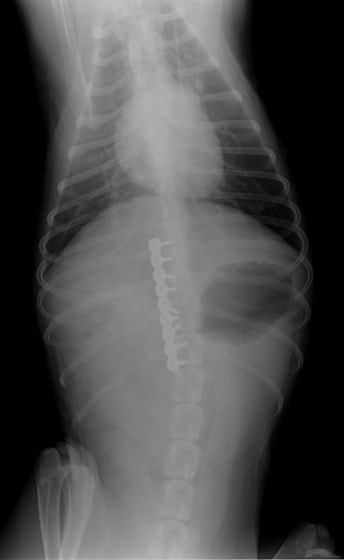

症例:交通事故による椎体脱臼

柴犬:9歳、避妊雌

交通事故直後、胸腰部に激しい疼痛、両後肢に完全麻痺を認め、シェフシェリントン徴候を呈していました。レントゲン検査において、第11-12胸椎間の脱臼が認められました。